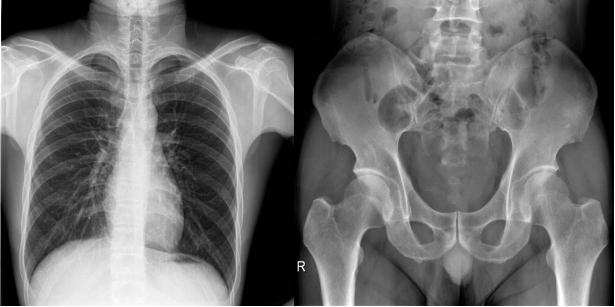

【固定懸吊dr-PLD7800E部分臨床效果圖】